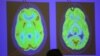

One hemisphere of a healthy brain (L) is pictured next to one hemisphere of a brain of a person suffering from Alzheimer disease.